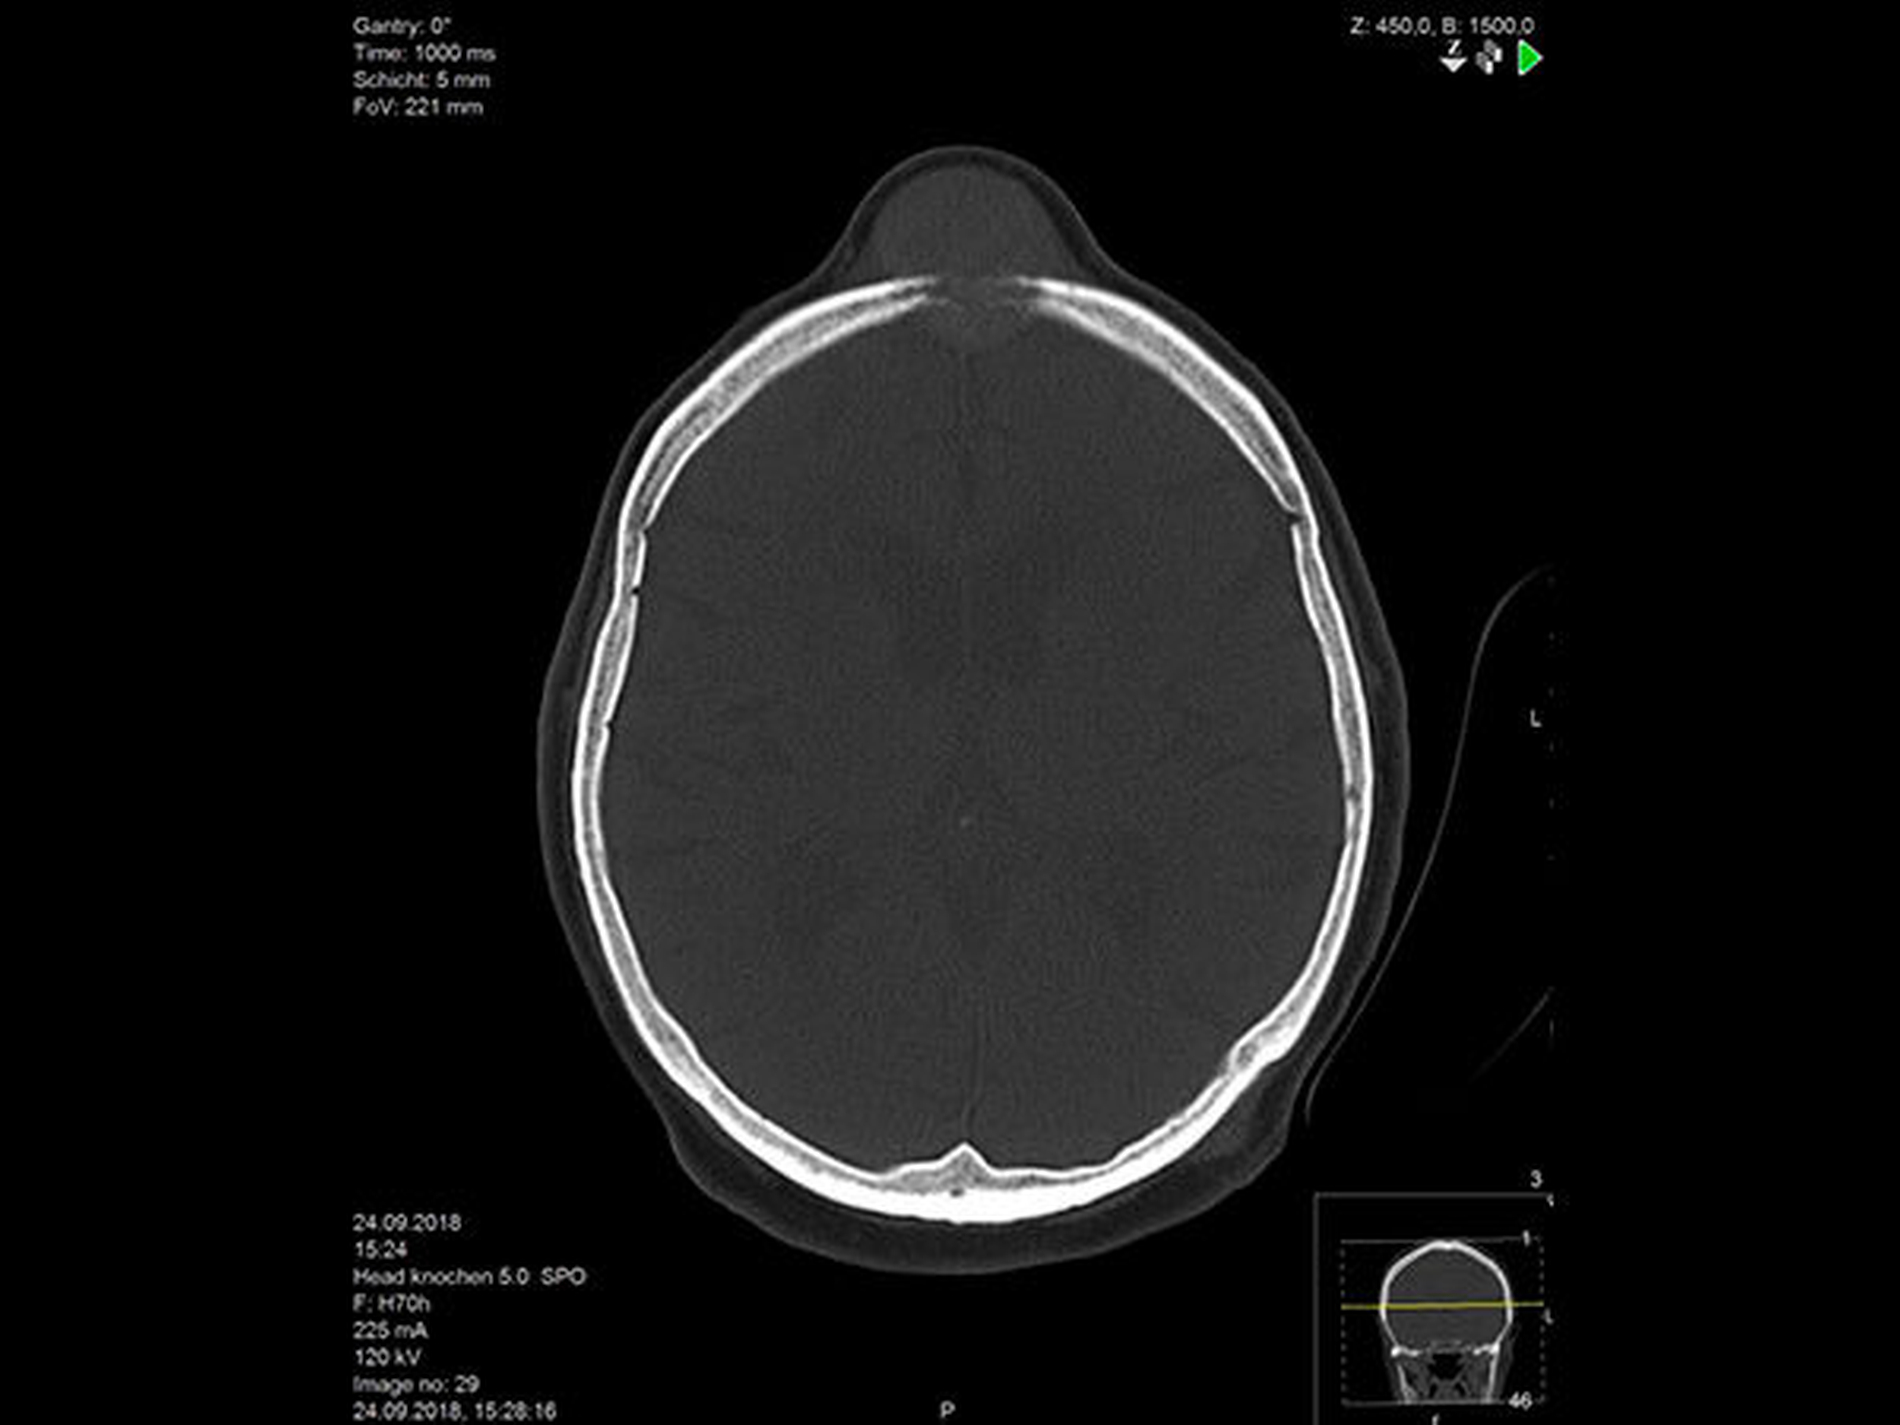

Nach Befundbesprechung mit der Patientin, Einwilligung zur Probenentnahme wird diese nach kranialer CT-Diagnostik in Lokalanästhesie durchgeführt. In der CT-Befundung zeigt sich ein infiltrativ wachsender Prozess, die Kalotte ist osteolytisch verändert, eine Alteration des Sinus sagittalis superior ist wahrscheinlich (Abbildung 2).